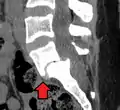

X-ray of a grade 4 anterolisthesis at L5-S1 with spinal misalignment indicated

Classification by degree of the slippage, as measured as percentage of the width of the vertebral body:[14] Grade I spondylolisthesis accounts for approximately 75% of all cases.[6]

- Grade IV: 75–100%

- Grade V: greater than 100%